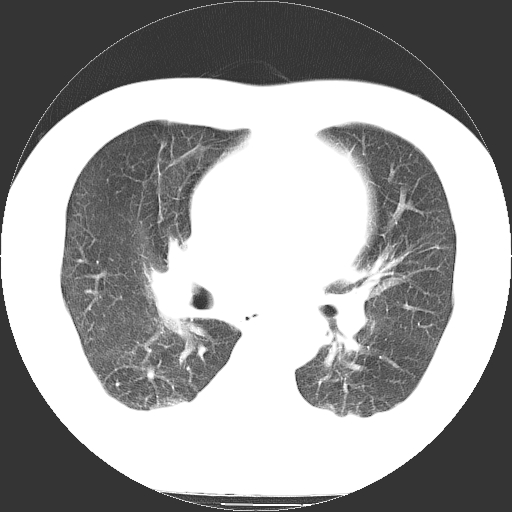

标题: CT21804:男,65岁,咳嗽、咳痰、发热5天。 [打印本页]

男,65岁,咳嗽、咳痰、发热5天。

慢支 肺间质纤维化合并感染!

支气管扩张合并感染,胸膜肥厚

考虑慢支并感染,肺间质纤维化。

两肺间质性炎症并感染

慢支,肺心病

支持慢性支气管炎伴感染,双侧少量胸腔积液.

两肺间质纤维化,支扩合并感染,双侧胸腔积液

感染,肺间质纤维化。

慢支 肺间质纤维化合并感染

支持慢性支气管、肺间质纤维化合并感染。

慢性支气管炎并感染,支扩,双侧少量胸腔积液.